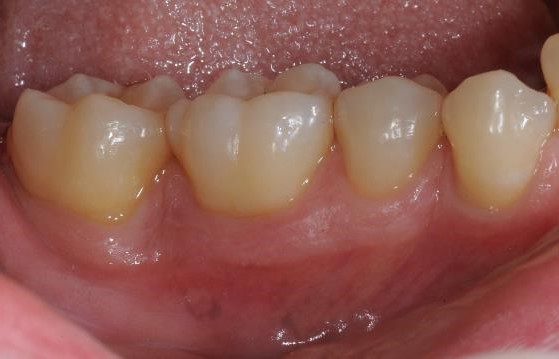

01/22 - Pre-surgical clinical situation, buccal view.

Deep intrabony defects treated using Straumann® Emdogain® - Dr. M. Stefanini